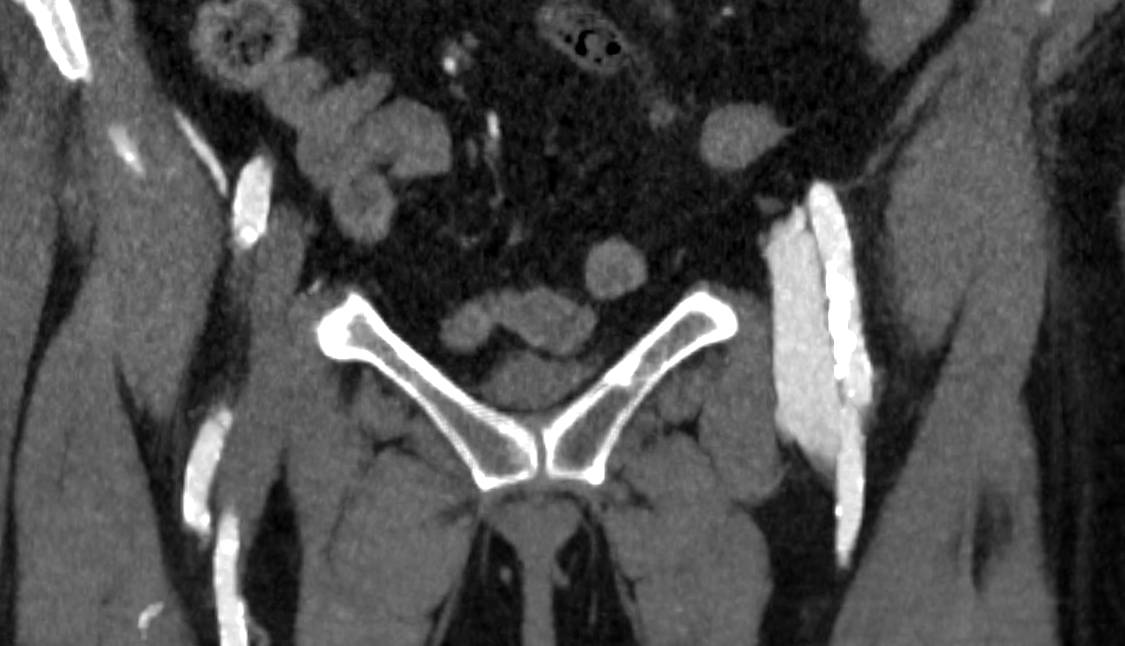

364f9ccde92724392db870ef40897531.png